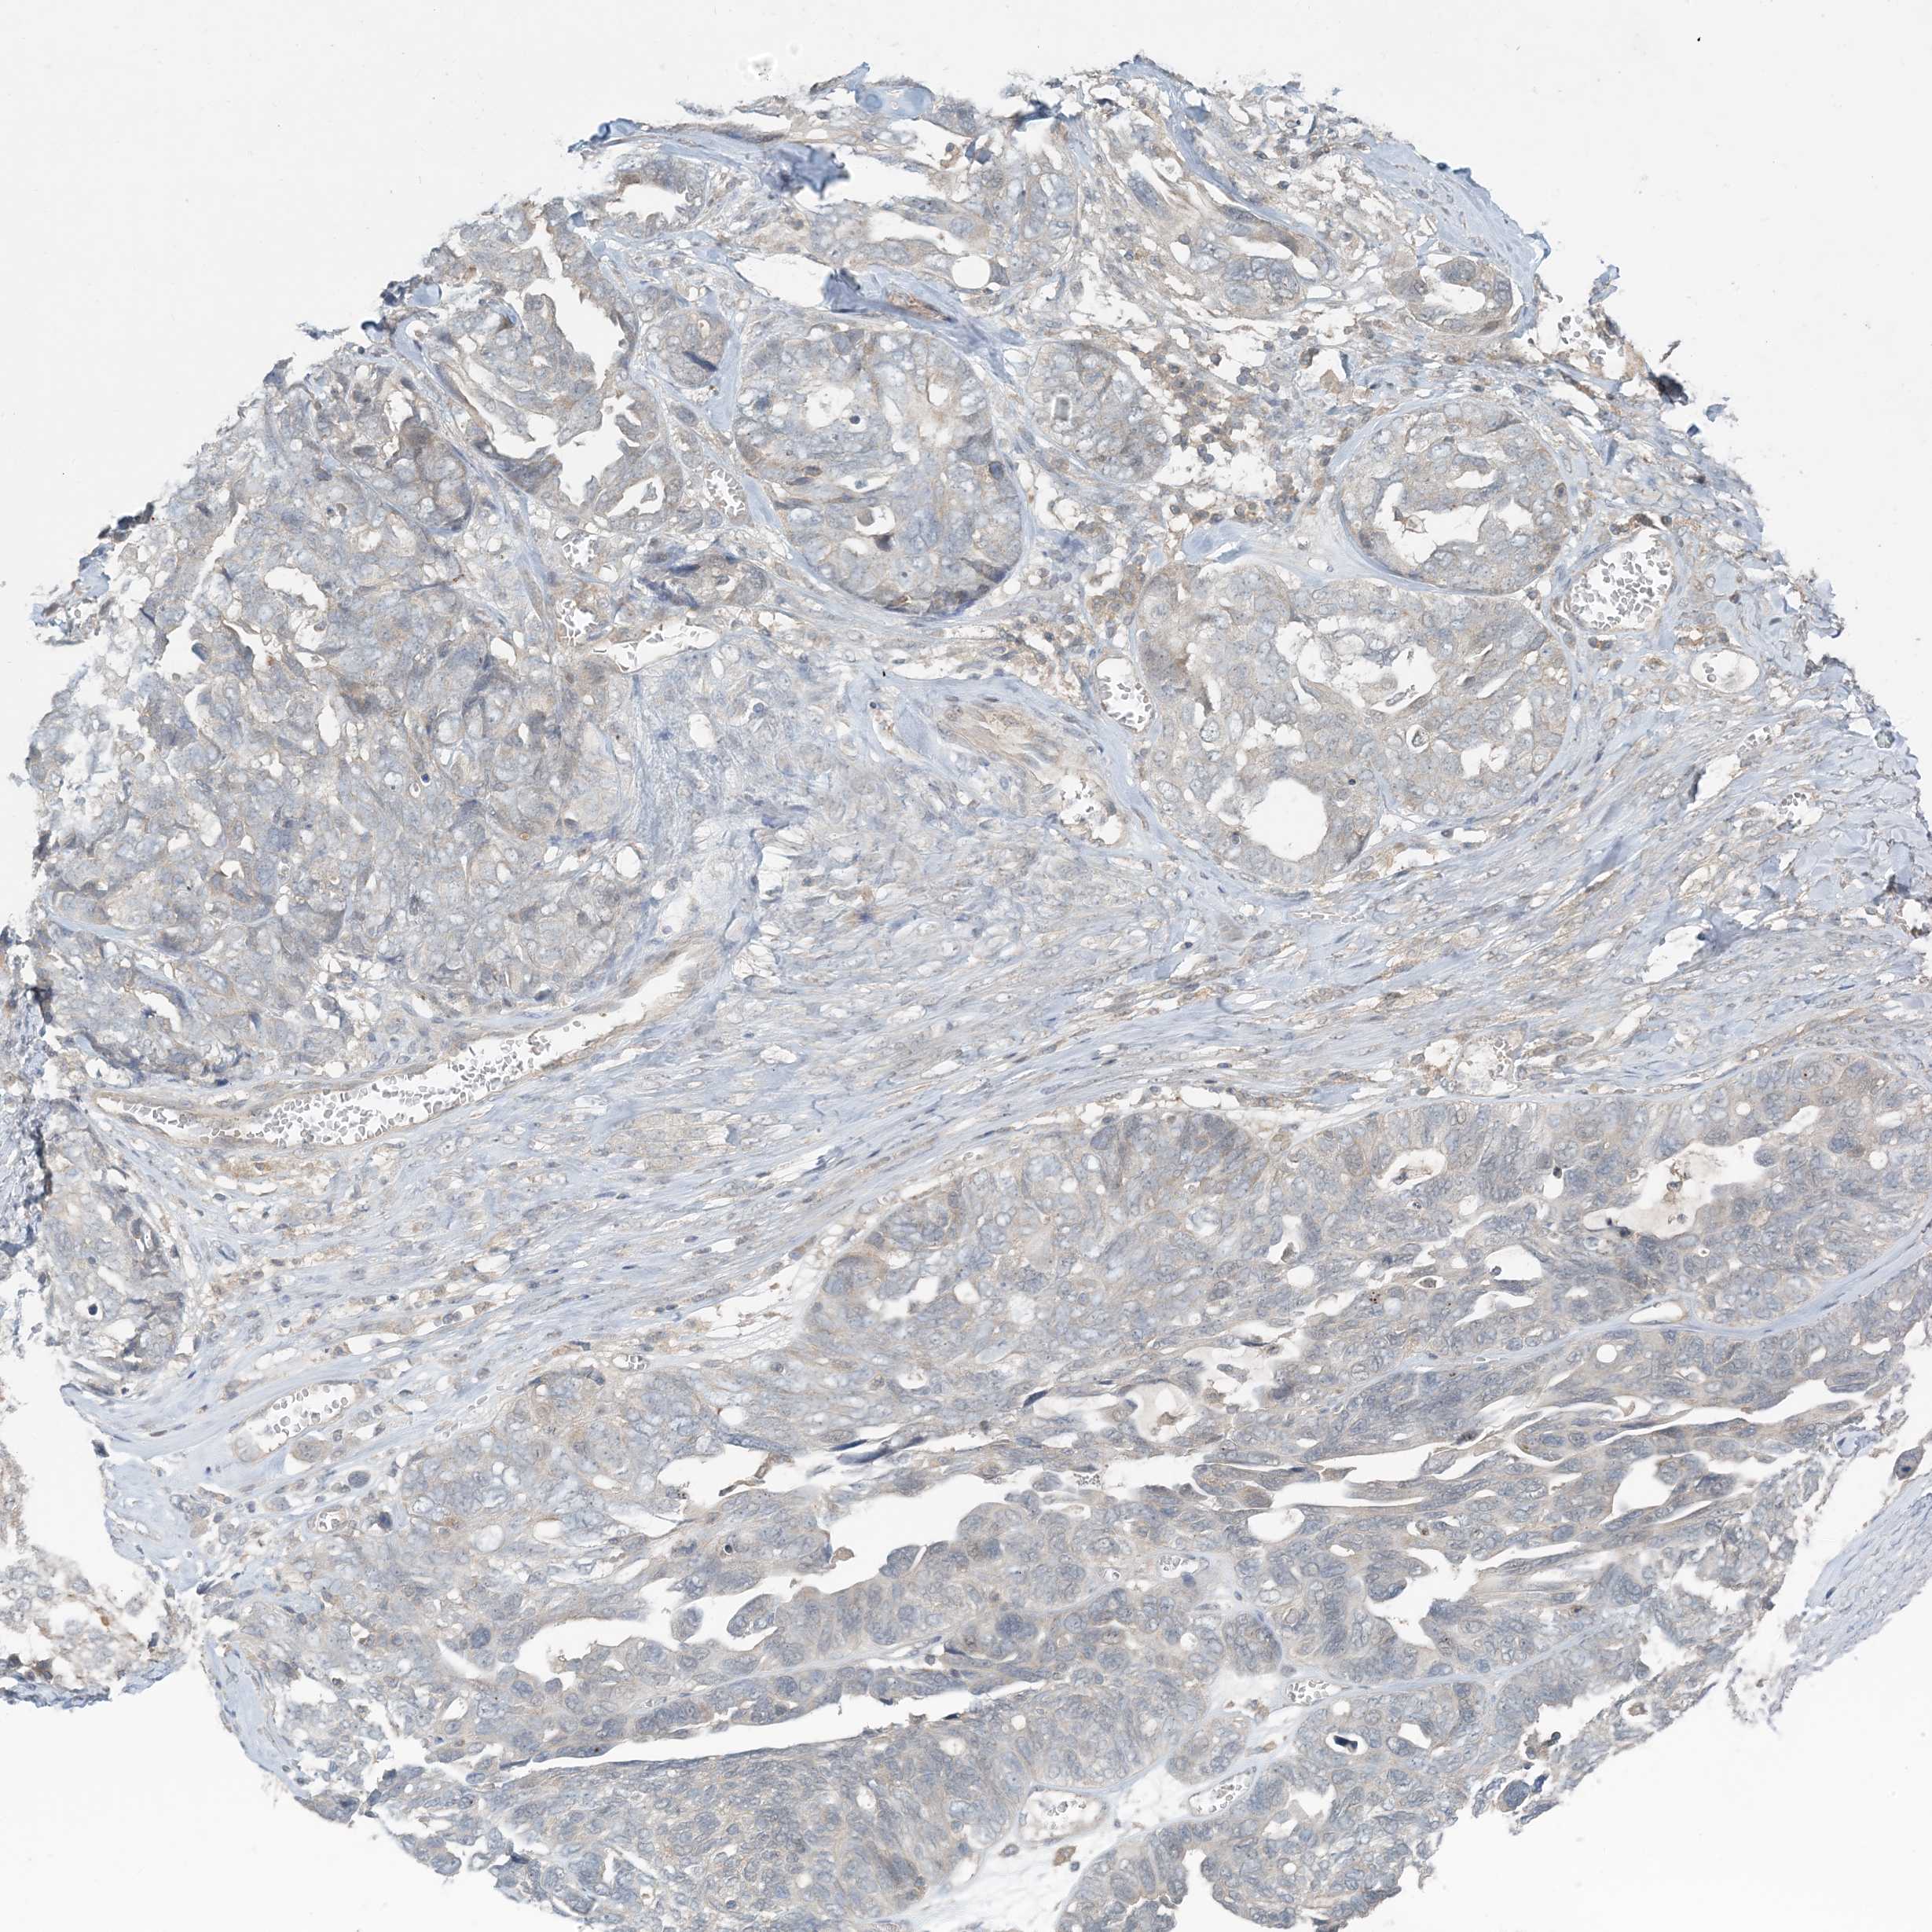

OVARIAN CANCER - Protein expressioni

A mouse-over function shows sample information and annotation data. Click on an image to view it in a full screen mode. Samples can be filtered based on level of antibody staining by selecting one or several of the following categories: high, medium, low and not detected. The assay and annotation is described here.

Note that samples used for immunohistochemistry by the Human Protein Atlas do not correspond to samples in the TCGA dataset.

Antibody stainingi

Antibody staining in the annotated cell types in the current human tissue is reported as not detected, low, medium, or high, based on conventional immunohistochemistry profiling in selected tissues. This score is based on the combination of the staining intensity and fraction of stained cells.

Each image is clickable and will lead to virtual microscopy that enables deeper exploration of all samples and also displays staining intensity scores, fraction scores and subcellular localization as well as patient and tissue information for each sample.

Antibody HPA034785

Antibody HPA034786

Cystadenocarcinoma, serous, NOS

Carcinoma, endometroid

Cystadenocarcinoma, mucinous, NOS

Carcinoma, NOS